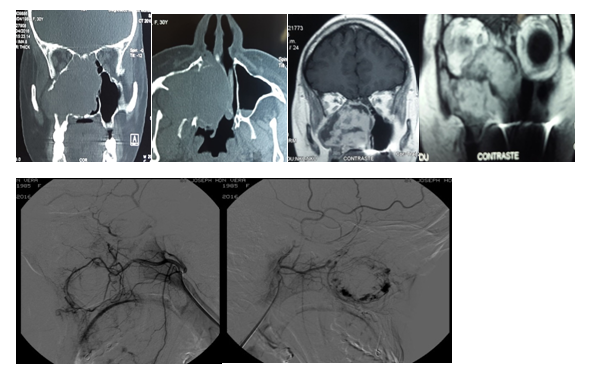

Four patients were treated for nasal cavity (1/4) and paranasal sinuses (3/4) hemangiomas through an endonasal approach with endoscopes between June 2006 and December 2016, at the Hospital Italiano de Buenos Aires. Three were men and one woman, the youngest was 36 and the oldest 65 years, the average age was 46.6 years. The main reason for consultation was unilateral (1/3), bilateral (1/3) nasal obstruction, and epistaxis (1/3). One patient also had epiphora, and proptosis was detected in two. In one of the patients, the hemangioma was a finding in a tomography requested to complete the evaluation for sleep apnea. Two tumors were located mainly in the maxillary sinus (one right and one left), displaced the eye and one had involved of the both nostrils and it spread to rhinopharynx. Another was located in the posterior ethmoid and another in the nasal cavity. In the 2 patients with giant tumors located in the maxillary sinus, endonasal biopsies were performed. One of the patients required a nasal tamponade due to significant bleeding.

The histopathological diagnosis was cavernous hemangioma, and in the other: complicated hemangioma with thrombosis and chronic inflammation. The other two patients underwent transnasal endoscopic resection and intraoperative histopathological study by freezing the surgical specimen. In the patient with the maxillary hemangioma, who presented an important epistaxis after the biopsy, a digital angiography with embolization was performed 48 hours before the surgery. In the 2 patients with hemangiomas of the maxillary sinus a medial maxillectomy, middle turbinectomy and anterior and posterior ethmoidectomy were performed (Figures 1&2).

Figure 2 Maxillary sinus hemangioma treated by endonasal approach Embolization performed 48 hours prior to surgery.